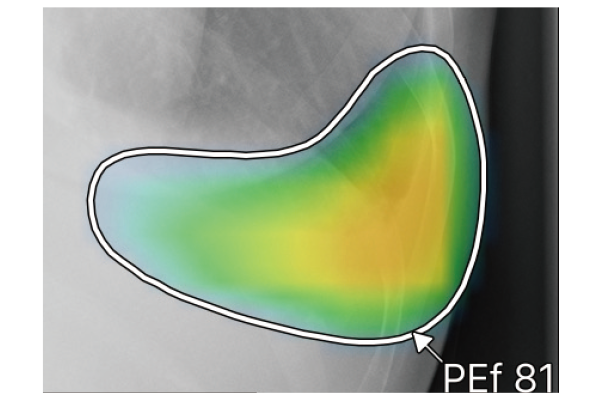

CXR-AIDが候補領域の解析をおこなったのち、0~100に応じた確信度を色分けして表示。

ヒートマップと輪郭の表示は3パターンから選択可能です。